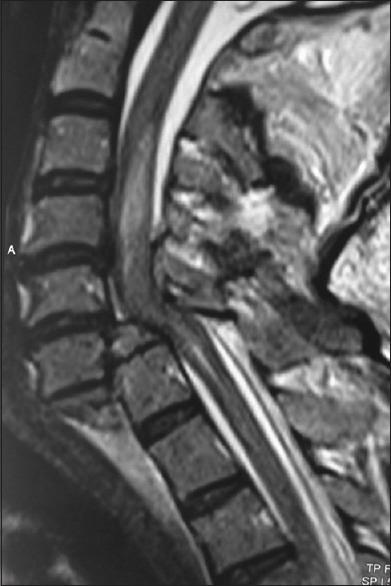

The success and popularity of the transforaminal approach in the lumbar spine have been made possible by the routine use of pedicle screws in the lumbar spine. Transforaminal approach in the cervical spine can give access to the disc and the vertebral body anteriorly and avoid an additional anterior approach in certain clinical situations. A case of cervical spine trauma was managed by this approach. Technical details and difficulties faced were analyzed in this article. Transforaminal approach in the lower cervical spine, though has a learning curve, seems to be a feasible technique along with the use of cervical pedicle screws. The safety and reproducibility of the approach need to be substantiated with a larger study. Further, this procedure can avoid additional anterior surgery in certain situations in the cervical spine.

腰椎经椎间孔入路的成功与普及得益于腰椎椎弓根螺钉的常规使用。颈椎经椎间孔入路可在前方显露椎间盘和椎体,在某些临床情况下可避免额外的前路手术。本文报道了1例采用该入路治疗的颈椎创伤病例,并分析了其技术细节及遇到的困难。下颈椎经椎间孔入路虽有学习曲线,但结合颈椎椎弓根螺钉使用似乎是一种可行的技术。该入路的安全性和可重复性需要通过更大规模的研究来证实。此外,该手术在某些颈椎情况下可避免额外的前路手术。